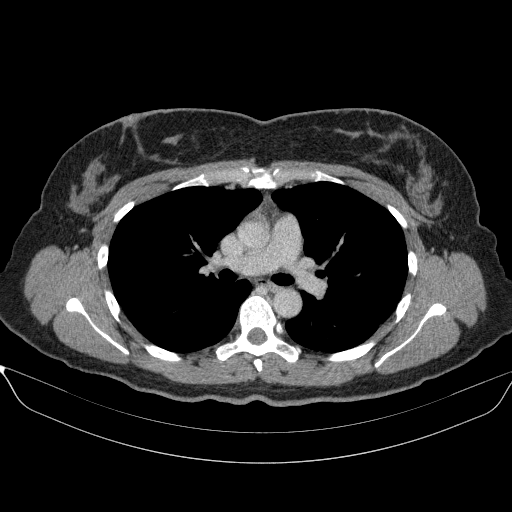

Original VENOUS CT scan

Full window (WL 1023.5, WW 4095 β†’ Low βˆ’1024, High +3071)

Lung window (WL -600, WW 1500 β†’ Low βˆ’1350, High +150)

Mediastinum window (WL 40, WW 400 β†’ Low βˆ’160, High +240)